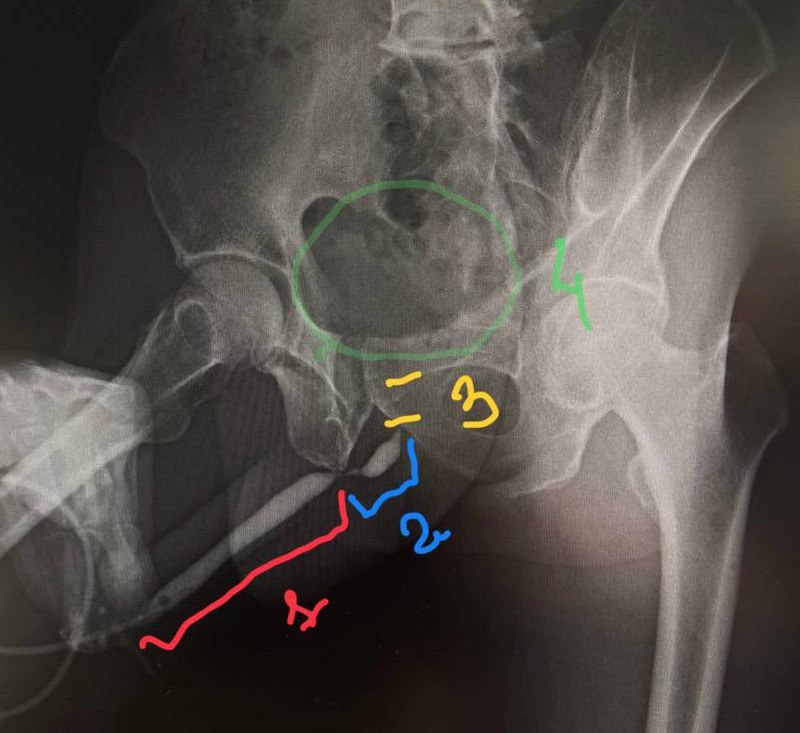

В ответ на пост 1 - пенильный отдел, 2 - бульбозный отдел (где и есть основная проблема), 3 - предполагаемая область нахождения мембранозного отдела (контраст не попал - пациент мог зажаться во время ретроградной уретрографии), 4 - мочевой пузырь (должен быть там). Правильный ответ - дистальный бульбозный отдел уретры.

1 - пенильный отдел, 2 - бульбозный отдел (где и есть основная проблема), 3 - предполагаемая область нахождения мембранозного отдела (контраст не попал - пациент мог зажаться во время ретроградной уретрографии), 4 - мочевой пузырь (должен быть там).

Правильный ответ - дистальный бульбозный отдел уретры.